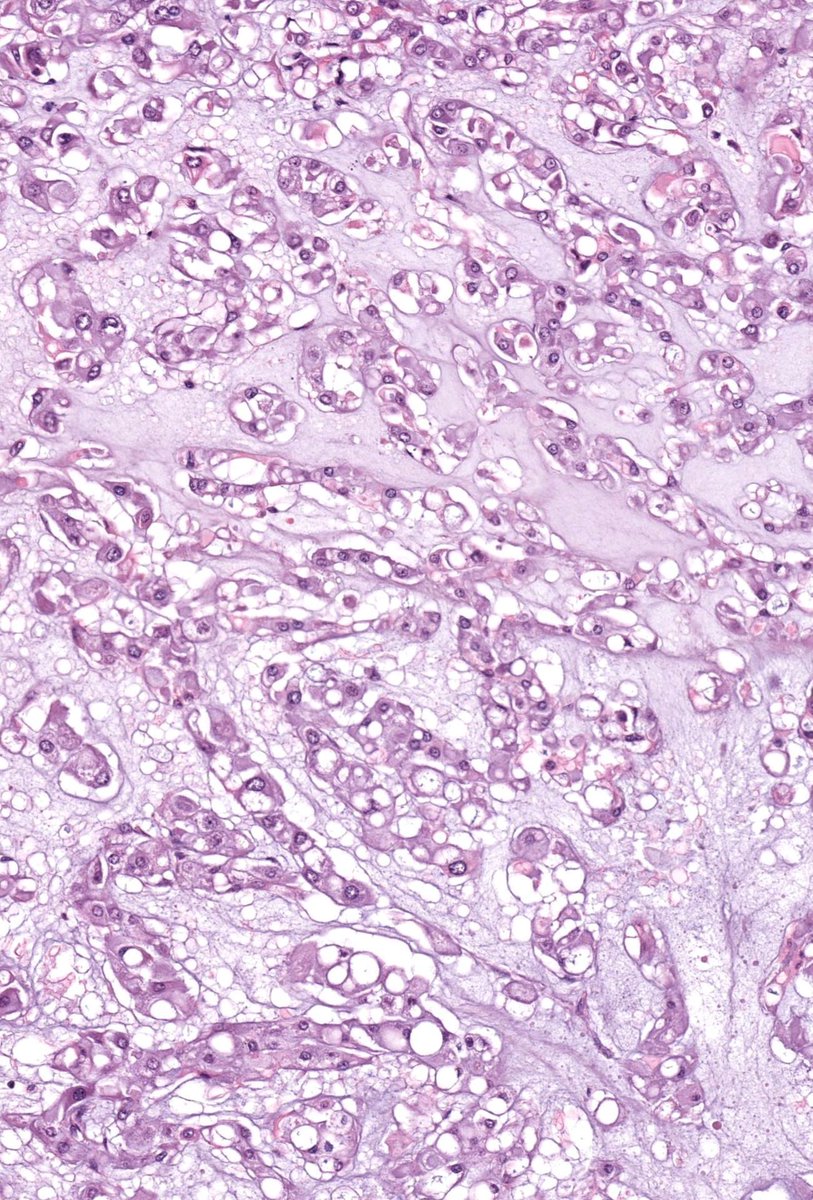

Researchers long believed they knew the answer to these questions: that immune cells mature through a process called central immune tolerance (see image). However, our immune system turned out to be more complex than they believed. Mary Brunkow, Fred Ramsdell and Shimon Sakaguchi have been awarded the 2025 Nobel Prize in Physiology or Medicine for their discoveries concerning peripheral immune tolerance.